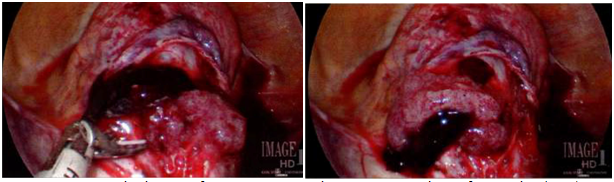

Surgical evaluation revealed an 8-week size, anteverted, mobile uterus with no additional masses; cervix was dilated to fingertip only. A 25mm skin incision was made in the umbilicus and a GelPOINT Mini advanced access single-site laparoscopy device was inserted. Abdominal insufflation revealed vesico-uterine adhesions limiting immediate visualization of the ectopic pregnancy. Due to poor visibility, intraoperative hysteroscopy was performed which revealed a gestational sac at the lower segment of the uterus, adherent to the anterior uterine wall approximately 3-4cm superior to the external cervical os. The RUMI manipulator was placed in the vagina without use of the uterine balloon. The vesico-uterine adhesions were lysed using the Harmonic scalpel and the ectopic pregnancy was exposed within the middle of the scar. Vasopressin was used for hemostasis and the Harmonic was used to incise this area; amniotic fluid with products of conception (POC) was noted and removed (Figure 1). Suction and graspers were used to remove as much POC tissue as possible. The RUMI manipulator was removed, and the endometrial tip was placed to ensure that the os was not closed during the repair. The uterine defect was closed in 3 layers using V-loc sutures (Figure 2). While maintaining observation with the abdominal camera, a suction D&C was performed. The diagnostic hysteroscopy, suction D&C, and SILS robotic resection of the CSEP was performed with an estimated blood loss of 30ml.

Figure 1 Intraoperative images of cesarean scar ectopic pregnancy; products of conception (POC) were noted and removed.